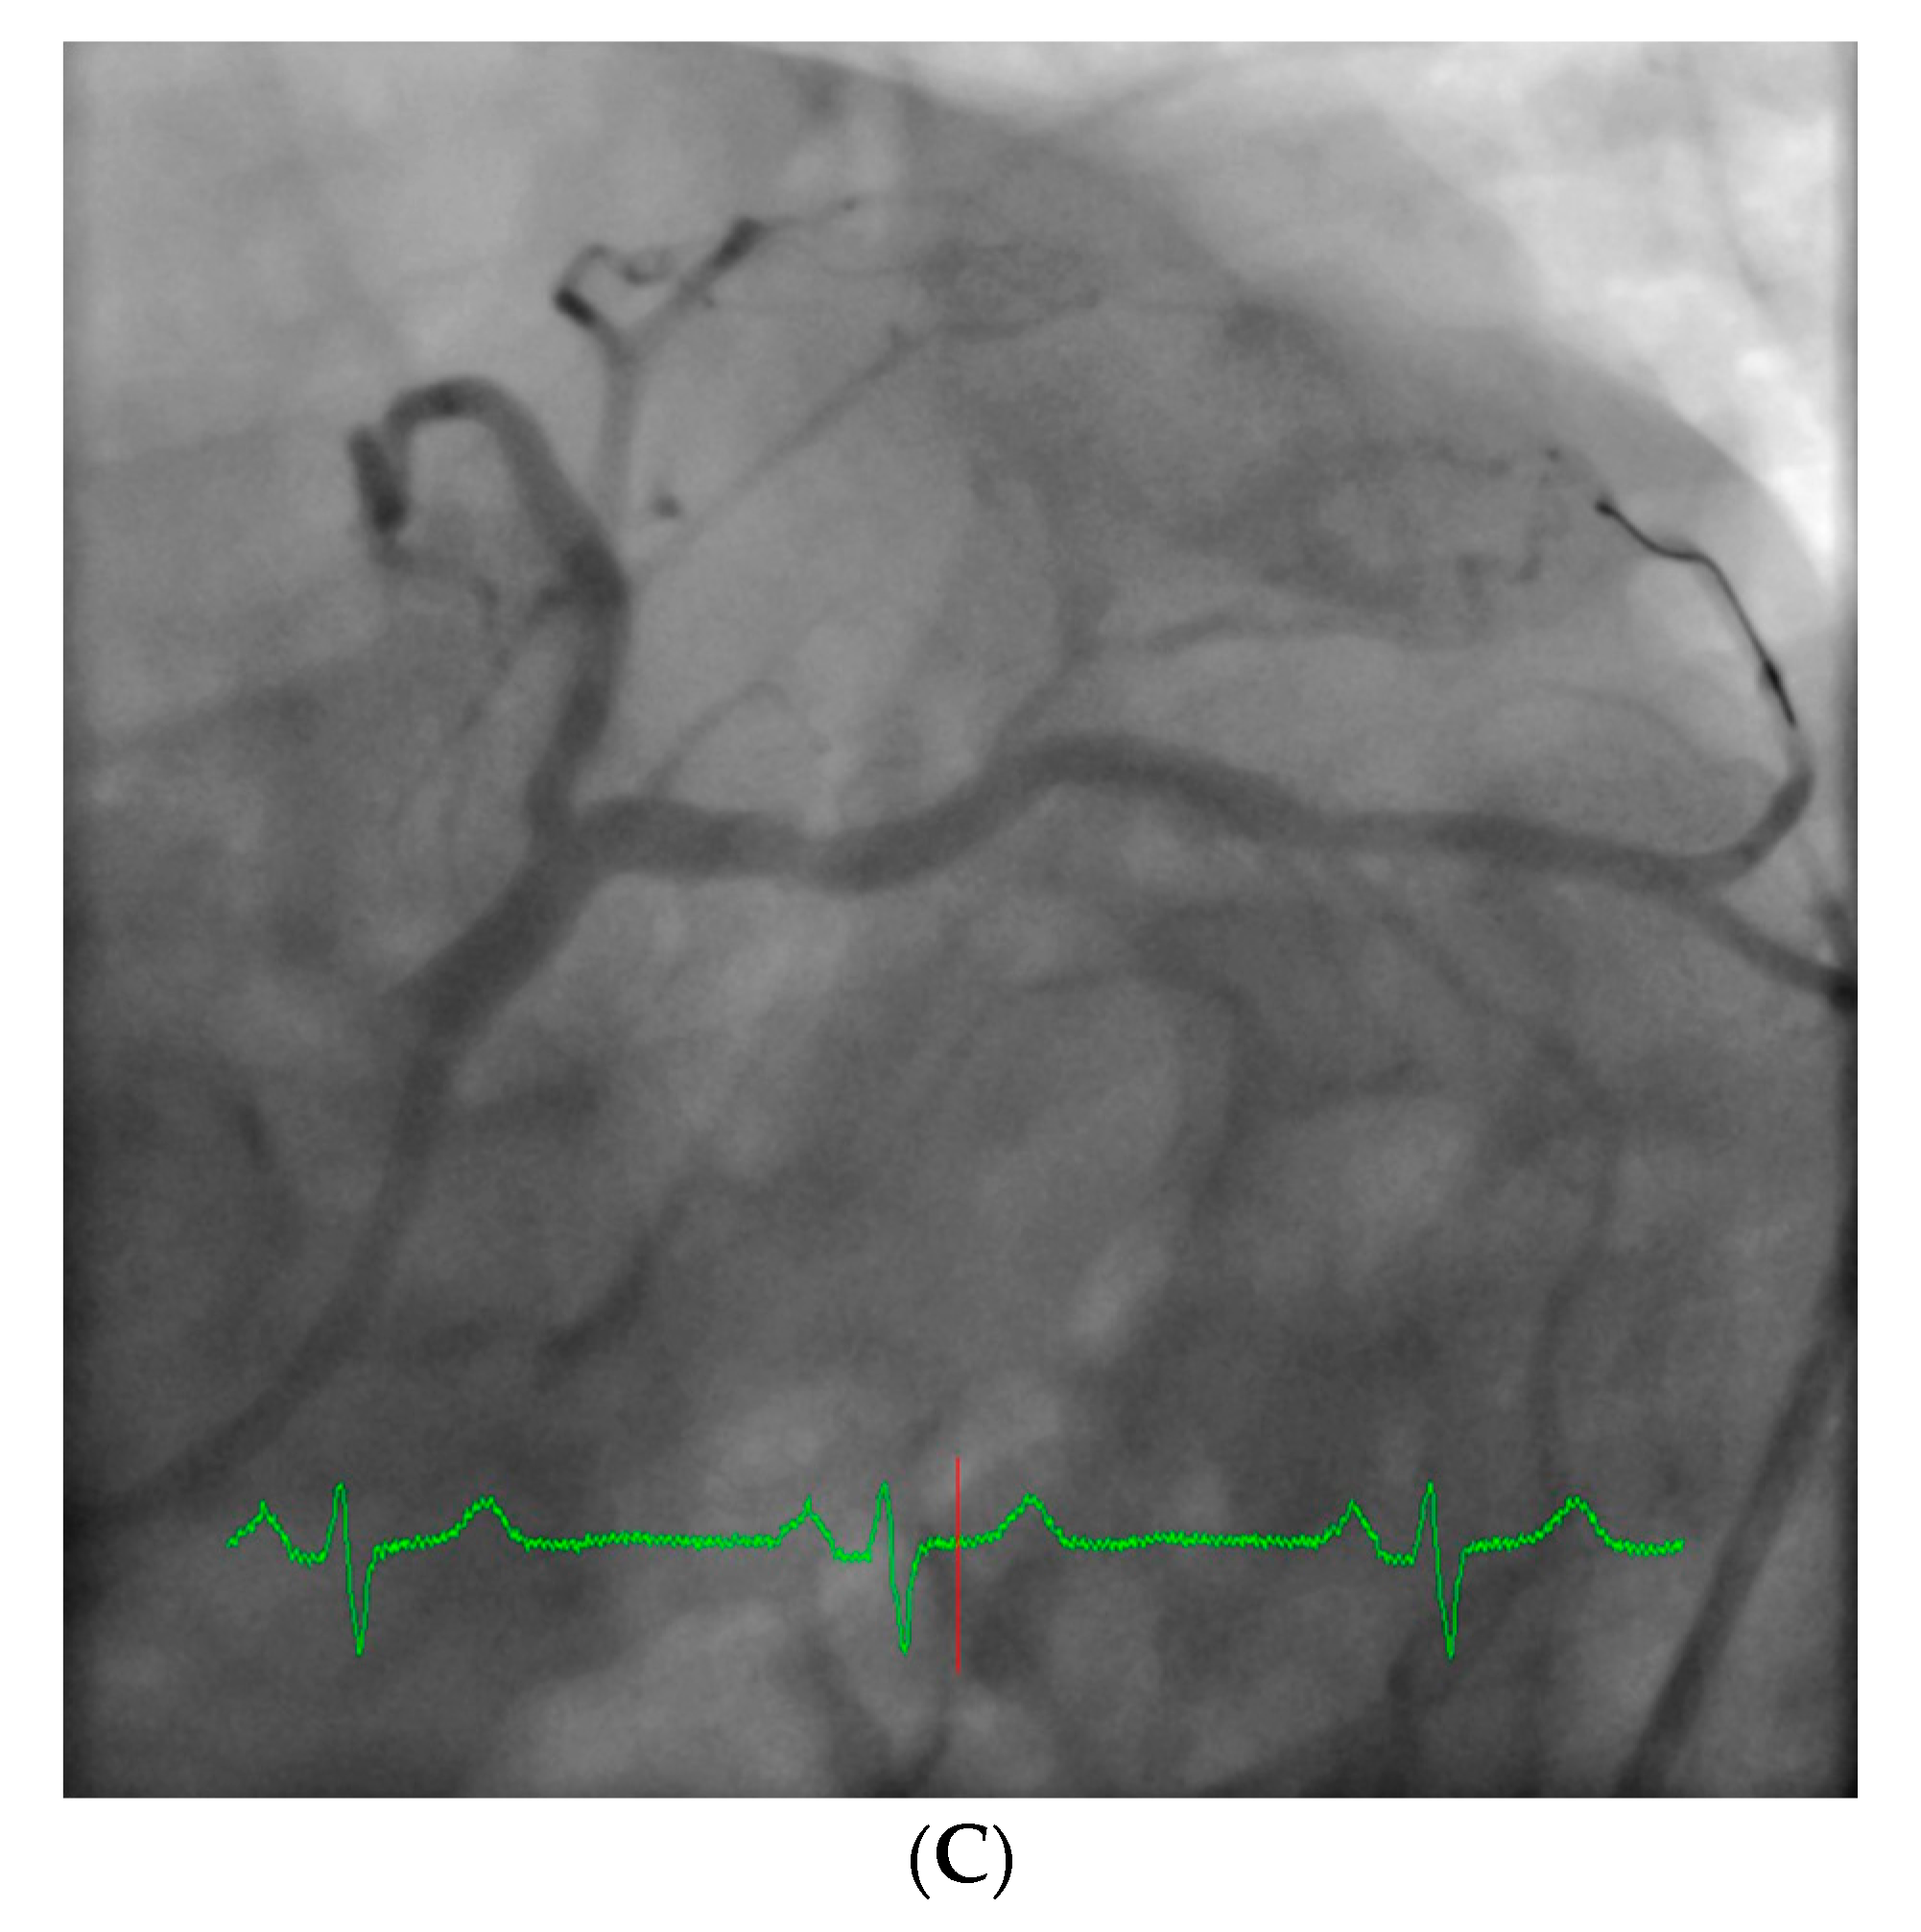

However, an ideal robotic intervention is one where the operator obtains access and performs initial guide placement manually, and is then able to complete the entire intervention from the cockpit without having to re-scrub, even briefly, to perform some portion manually. An example of an excellent case for robotic PCI is a two vessel PCI of the left anterior descending and circumflex arteries, where one guide shape and a single guidewire is used for both vessels, and where significant radiation exposure or a prolonged time in lead are both avoided. Figure 2 shows an example of an ideal robotic PCI case.

Figure 2. Example of an ideal case for robotic PCI. These images are from a 72 year-old with unstable angina referred to our hospital for intervention. Diagnostic catheterization showed moderate disease in the LAD (A) but with fractional flow reserve of 0.65 and severe disease of the LCX (B) with chronic occlusion of the RCA. The LAD and LCX were both treated successfully robotically with post-stent images shown in (C).